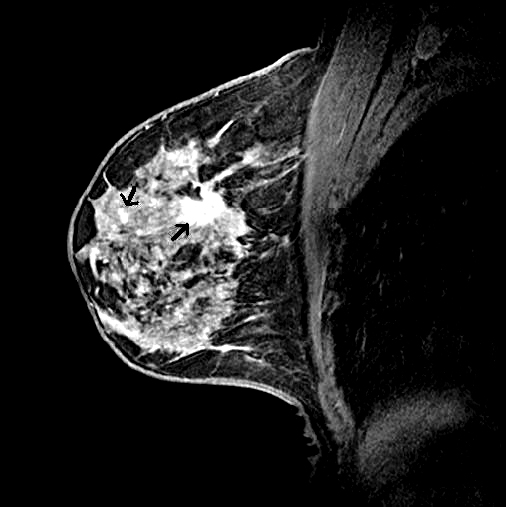

- Luego de ser diagnosticada con cáncer de mama se puede realizar una RMN del seno para determinar:Cuán grande es el cáncer y si involucra el músculo subyacente. Si hay otros cánceres en el mismo seno y si existe un cáncer insospechado en el seno opuesto. Si existe algún ganglio linfático anormalmente largo en la axila que podría indicar que el cáncer se ha desparramado hacia este sitio.

Con nuestra Nueva RM Digital podemos obtener resultados increibles incluso en pacientes inquietos, presencia de artefactos de movimiento y Contraste de agua, grasa, en fase y fuera de fase en una sola adquisición para obtener imágenes libres de grasa.

Con la nueva RM digital podemos obtener imágenes de cada mama con saturación de grasa y además adquirir imágenes bilaterales en plano axial o sagital, lo que nos ha permitido mejorar de forma notable nuestro programa de diagnóstico por imagen del cáncer de mama.”